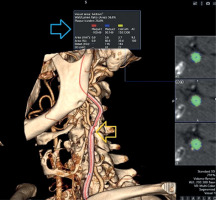

Figure 2

Three-dimensional (3D) volume-rendered and quantitative plaque analysis images of the same patient’s carotid arteries obtained by MDCTA. The yellow arrow indicates a non-obstructive plaque detected in the carotid artery. The blue arrow shows the analysis results for this plaque, including vessel cross-sectional area, plaque burden (26.8%), and plaque composition. Plaque 1 – low-density, soft; plaque 2 – mixed; plaque 3 – calcified